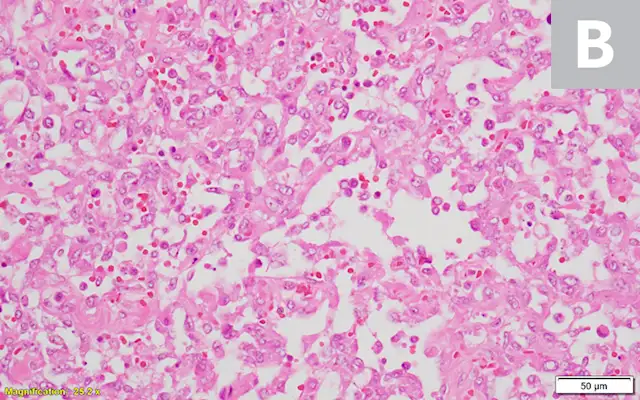

Abdominal and thoracic radiography (mass effect or pulmonary metastases; Figure 5)

Additional radiography studies of affected anatomic sites (Figure 7)